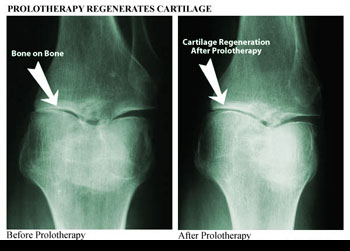

Used with permission

from Ross A Hauser, MD,

www.caringmedical.com

Prolotherapy involves injections of a mildly irritating

solution into the painful area. The irritant, usually a

dextrose-based solution, triggers the body's natural

healing response and causes the proliferation of new

collagen fibers, which are the building blocks of

ligaments and tendons. (The "prolo" in prolotherapy stands

for proliferative.) As tissue growth continues, the

ligaments and tendons become thicker and stronger,

regaining their ability to stabilize the joint and take

the pressure off sensitive nerve endings. Pain subsides,

range of motion returns, and cartilage degeneration slows

down.